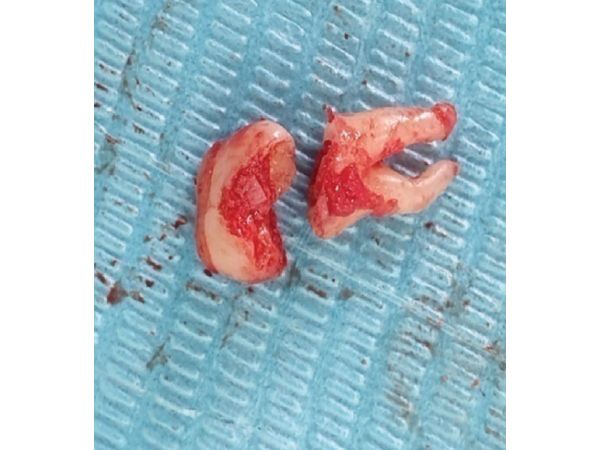

- Удалили кость над зубом, сам зуб разрезали хирургическим бором.

- С помощью прямого элеватора, который используется для вывиха и удаления корней, извлекли фрагменты зуба.